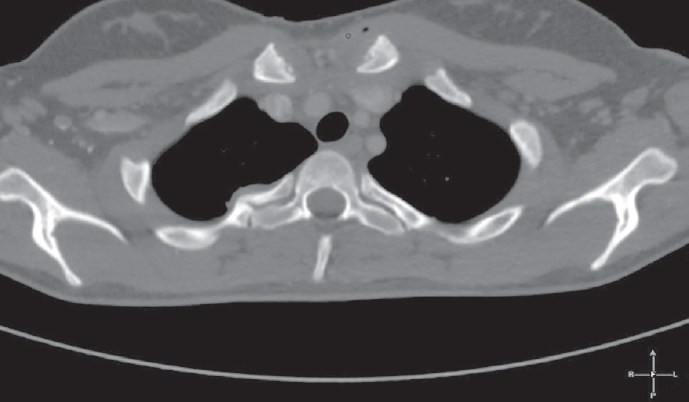

По данным компьютерной томографии от 31.12.14 — признаки выпотного плеврита с обеих сторон, более выраженного слева. Ателектазы в S9 с обеих сторон компрессионного характера. Лимфоаденопатия внутригрудных лимфатических узлов. Перикардит. Отмечается отек мягких тканей вокруг передних отделов ключицы с наличием мелких пузырьков газа. Выявленные изменения в головке левой ключицы соответствуют послеоперационным изменениям. Во всех третях правой почки прослеживаются множественные участки пониженного накопления неправильной треугольной формы, широким основанием прилежащие к капсуле почки, захватывающие кортикальный и медуллярный слои, наиболее вероятно являются проявлениями инфаркта правой почки. Отек паренхимы левой почки (рис. 1, 2).

Рис. 1. Компьютерная томограмма пациентки А., 16 лет. Изменения в головке левой ключицы

Fig. 1. CT scan of 16-year old female patient A. Changes in the head of the left clavicle